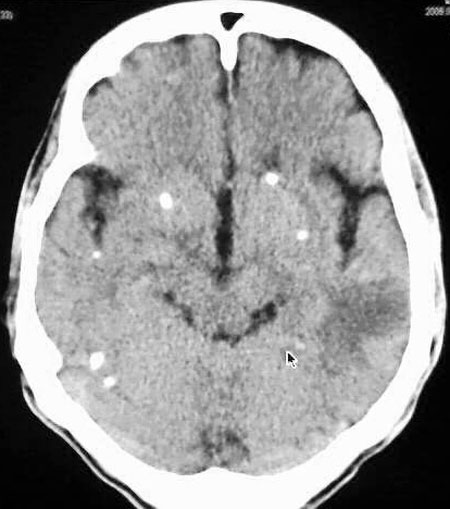

以下是引用守望可可西里在2006-9-6 8:01:00的发言:[br][br] “国内文献进行了脑囊虫病的ct分期:①活动期: ct标志为头节、囊壁、囊液同时存在,分为脑实质小囊型与脑室型;②退变死亡期:ct标志为头节消失、囊腔肿大、虫体崩解,分为单发或多发小囊型、大囊型、葡萄状囊丛型、脑炎型、脑内小脓肿型、脑梗塞型、脑膜炎性③钙化期:标志为囊虫灶转为高密度的钙化结节;④混合期:为活动期、退变期、钙化期病灶混合存在。”[br] 本病例左颞叶、右颞顶叶低密度影,无占位表现,病灶极似脑梗塞。但双侧病灶中偏边缘部位还是有圆形钙化灶,可以考虑为虫体钙化。再加上脑实质内见散在的不对称圆形钙化,其形态类似“大米粒状”,本例应该考虑是脑囊虫病,分期为混合期。